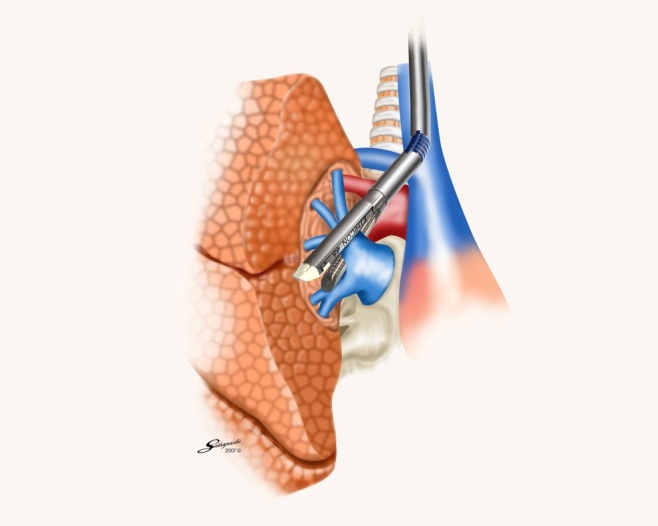

胸腔鏡手術の実際(右肺上葉切除時の自動縫合器使用例)

肺静脈切離

肺動脈切離

気管支切離

葉間切離

術中に使用しているデバイス

自動縫合器

カートリッジの仕組み